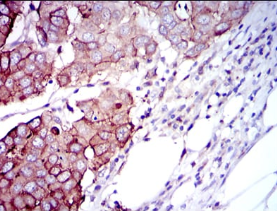

IHC    1/200 - 1/1000